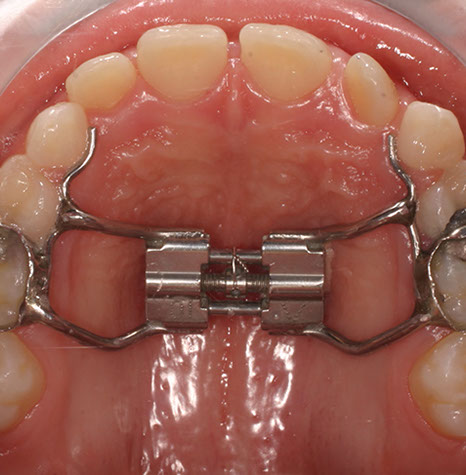

Talvolta, quando si vuole espandere l’arco palatino iposviluppato,  può essere necessario applicare un Diastasatore